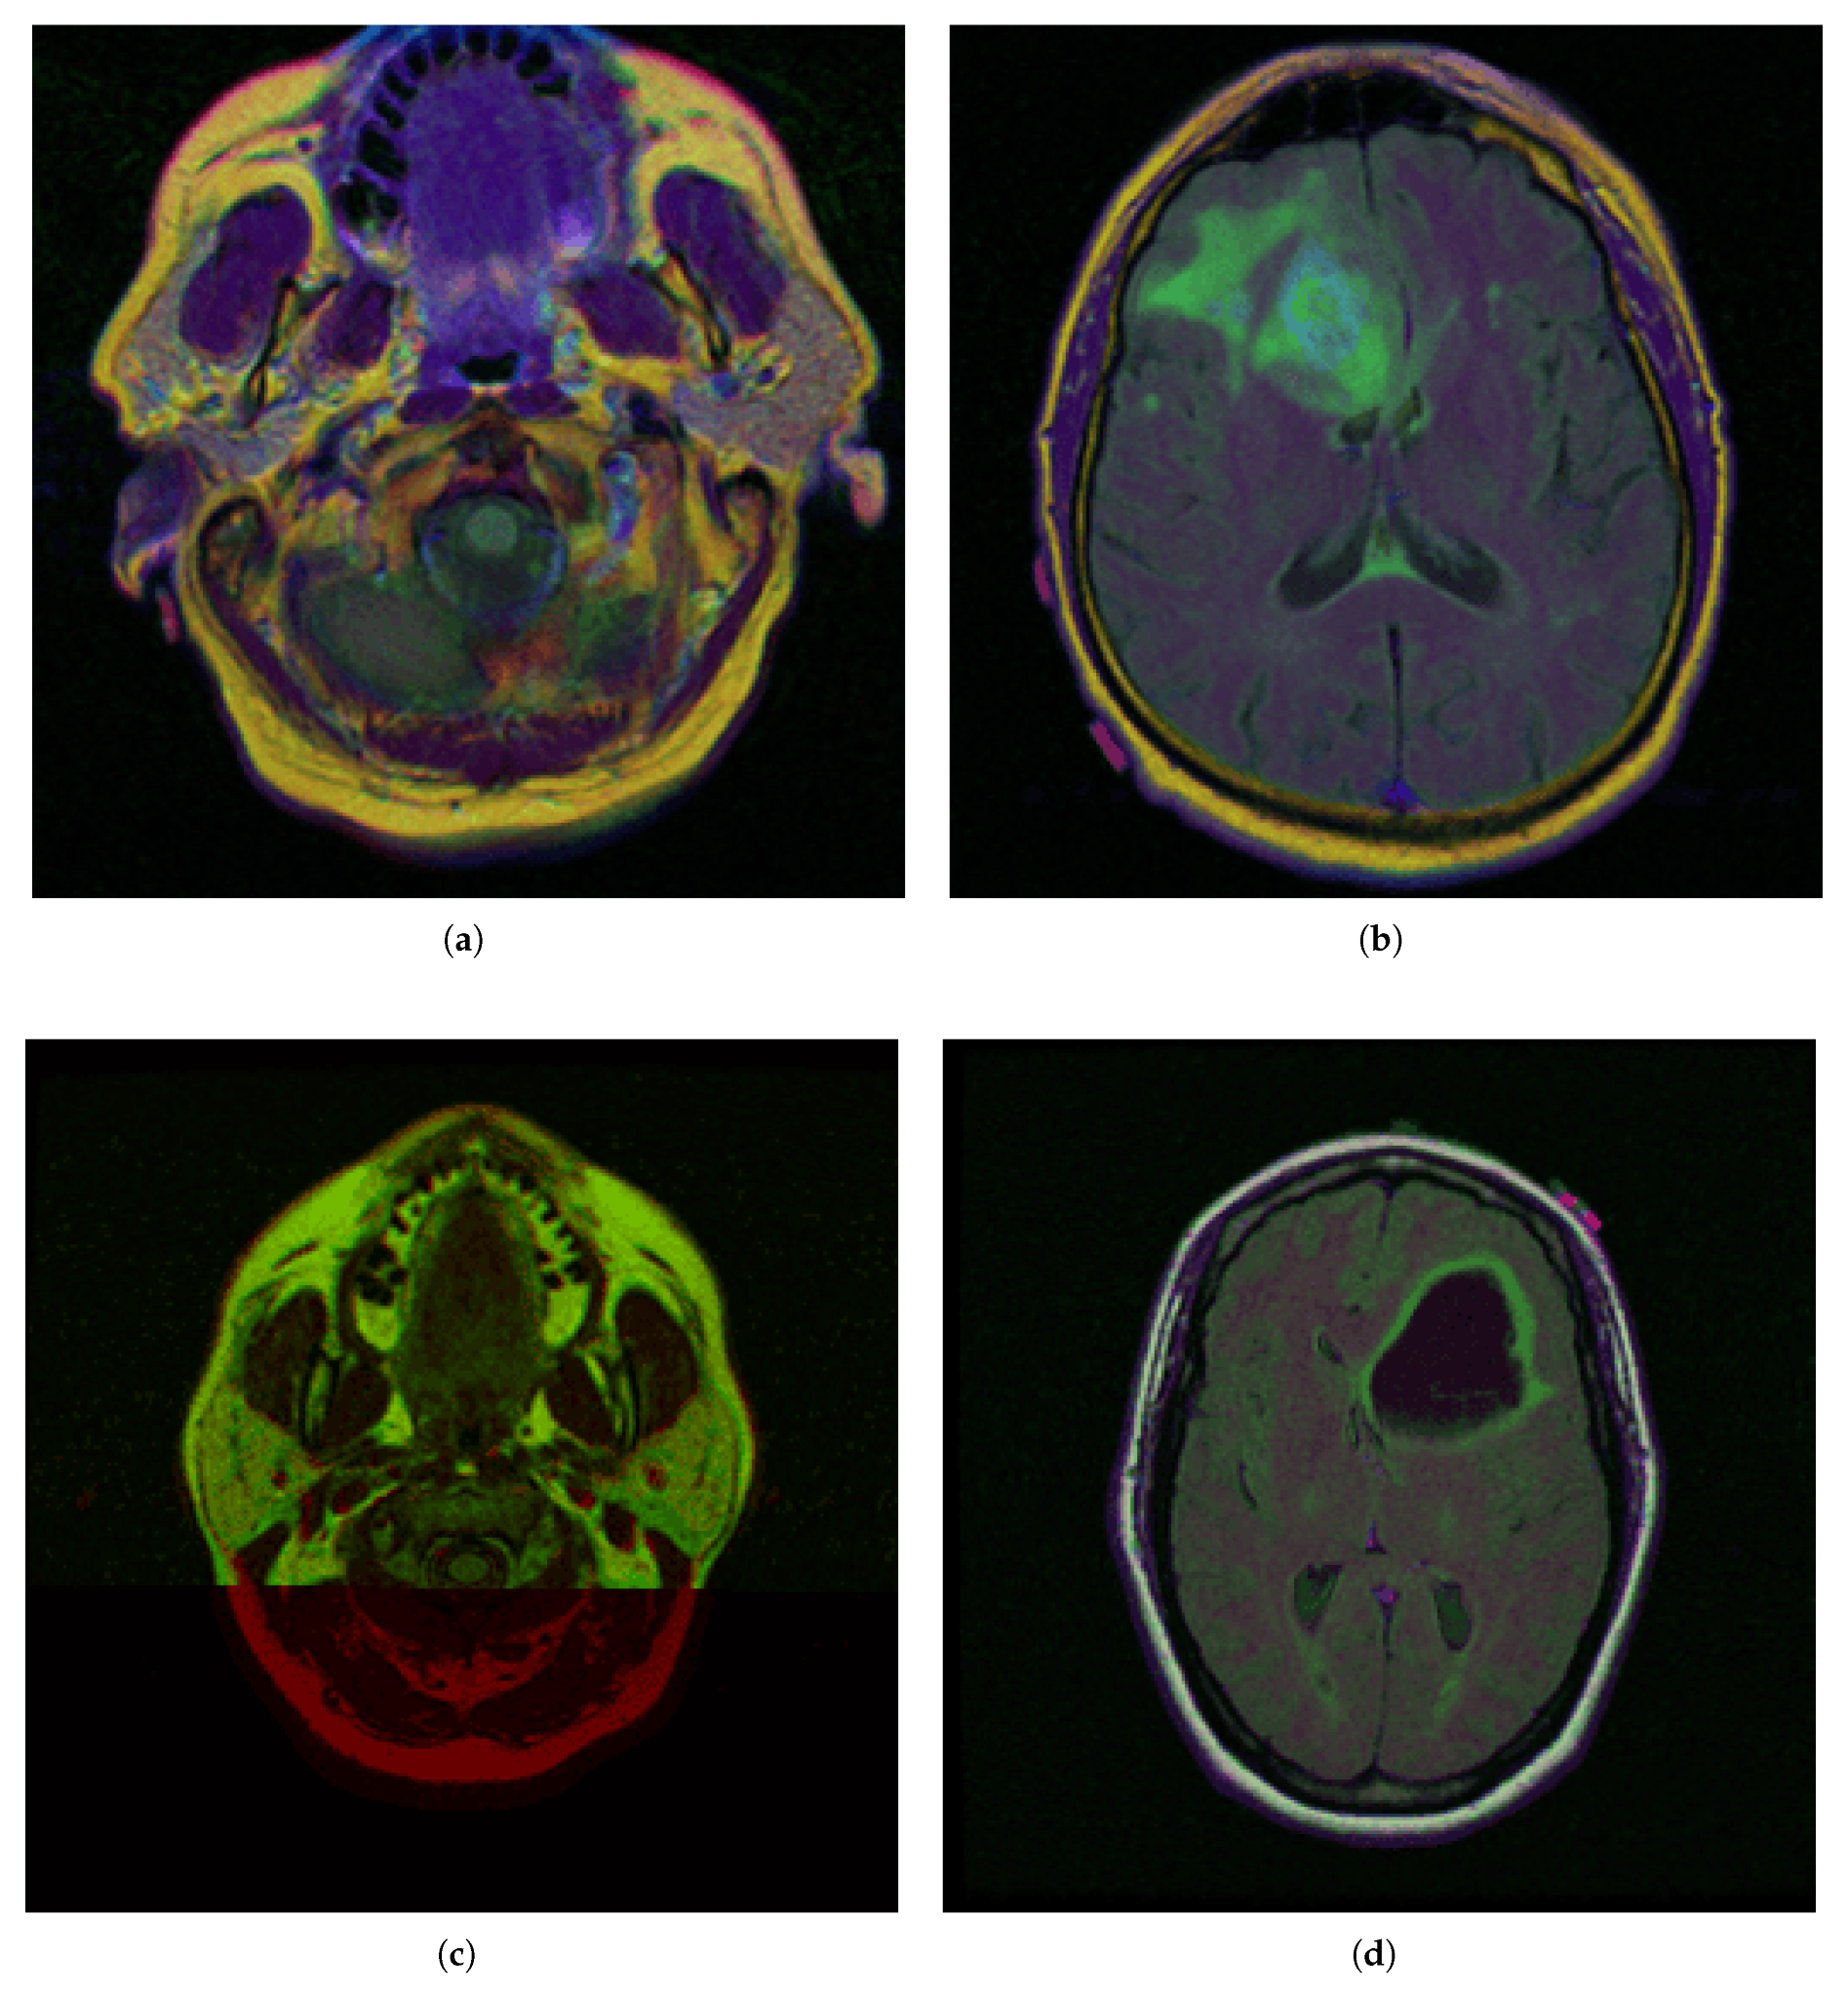

The comparative charts and visual presentation of edges allow for a detailed analysis of each algorithm’s strengths and weaknesses, offering insight into the trade-offs between edge completeness and false detection rates. Figure 4 illustrates the fuzzy C-means (FCM) clustering results obtained from the four case studies: CS1, CS2, DU1, and DU2. Each subfigure (A, B, C, and D) presents the following sequence:

-

Original Image: The initial input image from the dataset.

Enhanced Image: The result after applying image enhancement techniques to improve contrast and feature visibility, likely to support better clustering outcomes.

Clusters 1 to 4: The segmentation outputs, where the image has been partitioned into four distinct clusters. Each cluster highlights different regions based on pixel similarity, potentially corresponding to anatomical structures, tissues, or specific features of interest within the medical images.

Key Observation: Figure 4 and Figure A1 collectively showcase the clustering module’s capacity to aid in visual discrimination and structural interpretation across the studied medical cases.

Figure 4. Clustering with fuzzy C-means (FCM) results within iMIA platform: The clusters emphasize various structural and textural components, with some clusters isolating specific regions with clear edges and others focusing on more homogeneous areas. The segmentation reveals critical areas with varying intensity patterns, possibly indicative of different tissue types or pathological regions: TCGA_CS_4941_19960909_3 (CS1) (additional results are shown in Figure A1).

Figure A1. Clustering with fuzzy C-means (FCM) results within iMIA platform. (b) TCGA_CS_4941_19960909_14 (CS2), (c) TCGA_DU_5872_19950223_1 (DU1), (d) TCGA_DU_5872_ 19950223_35 (DU2) (refer to the image (a) CS1 result in Figure 4).